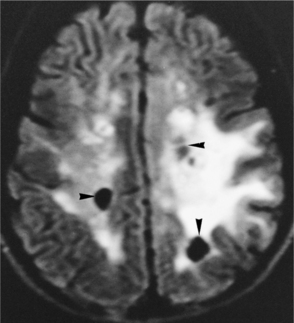

About 20% to 50% of adults with brain tumors develop seizure activity. The cerebral edema causes hyperactive cells, which produce abnormal, paroxysmal discharges or seizure activity.106 Seizures may be the first presenting sign of a tumor. In patients presenting with seizures, detection of low-grade gliomas is becoming increasingly frequent with magnetic resonance imaging (MRI). See Fig. 30-3 for an MRI scan of a low-grade glioma presenting with a seizure. In the later stages of illness, seizure activity is present in 70% of patients.93 A common feature of a tumor-related seizure is its repetitive nature, with seizures being very stereotypical in a given patient.137

Figure 30-3 Magnetic resonance imaging (MRI) of a low-grade glioma. A, T2-weighted image. B, T1-weighted image, gadolinium contrast with minimum enhancement. The images are typical of this tumor, which is being detected with increasing frequency by MRI in seizure patients. Many are invisible on computed tomographic scans. (From Goldman LM, Ausiello D, eds: Cecil textbook of medicine, ed 22, Philadelphia, 2004, Saunders.)